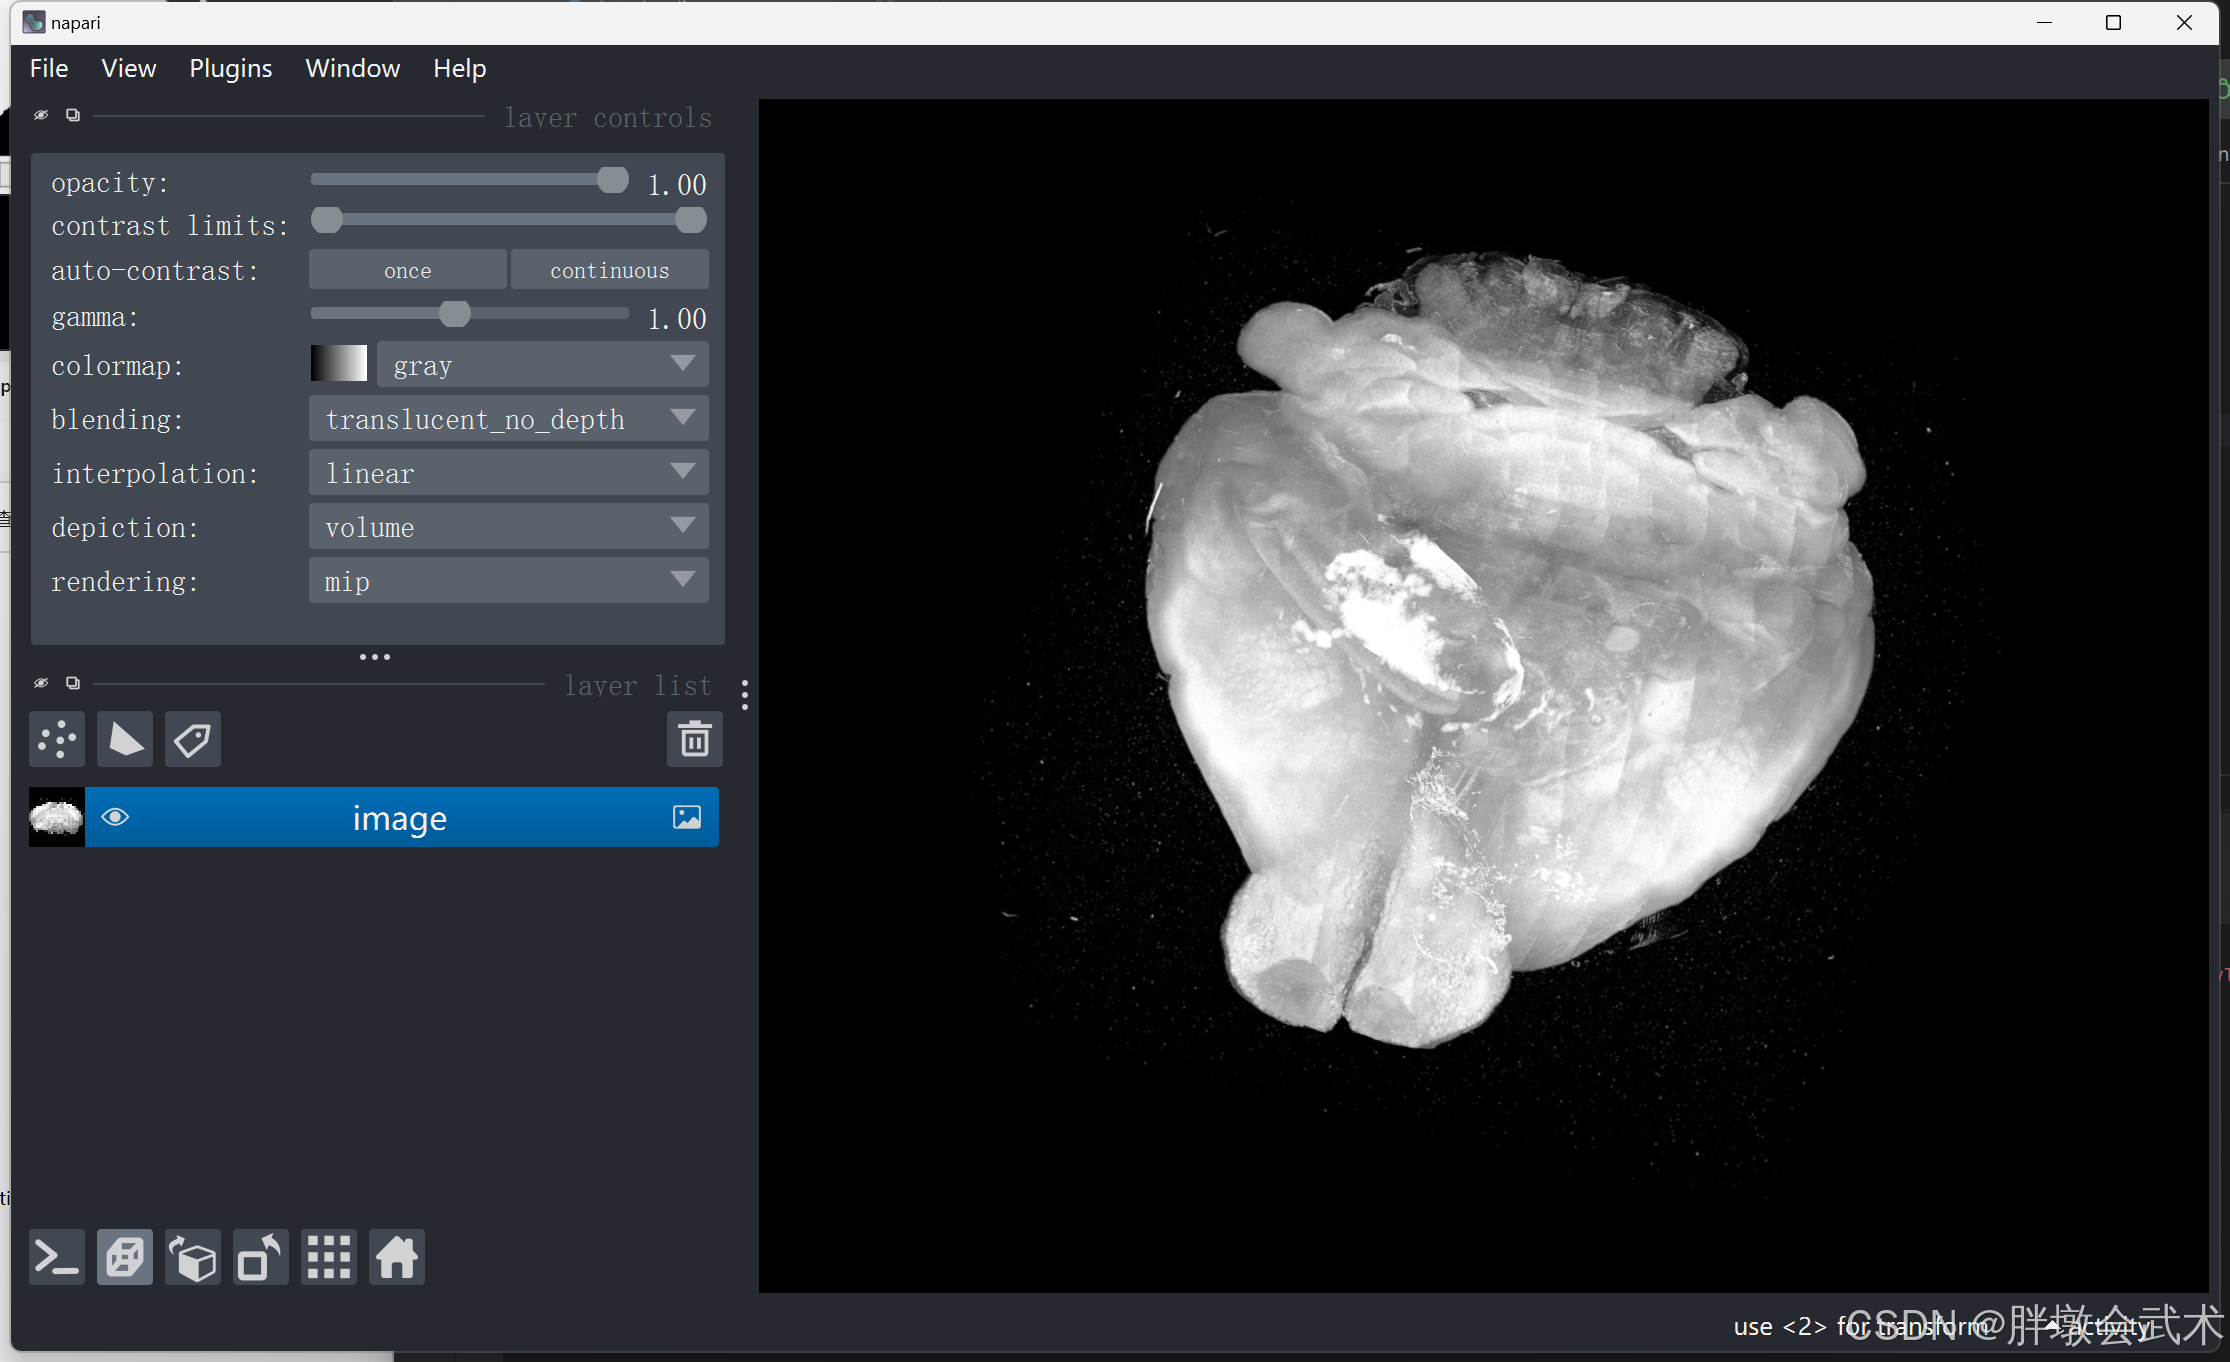

3.2.2、(自动)启动 n 维显示模式(Toggle ndisplay)

import napari

import tifffile

if __name__ == '__main__':

image_path = r'F:\py\image.tif'

image = tifffile.imread(image_path)

viewer = napari.Viewer() # 创建 napari 视图

viewer.add_image(image, name='image')

viewer.dims.ndisplay = 3 # 启动 n 维显示模式

napari.run() # 显示 napari 视图